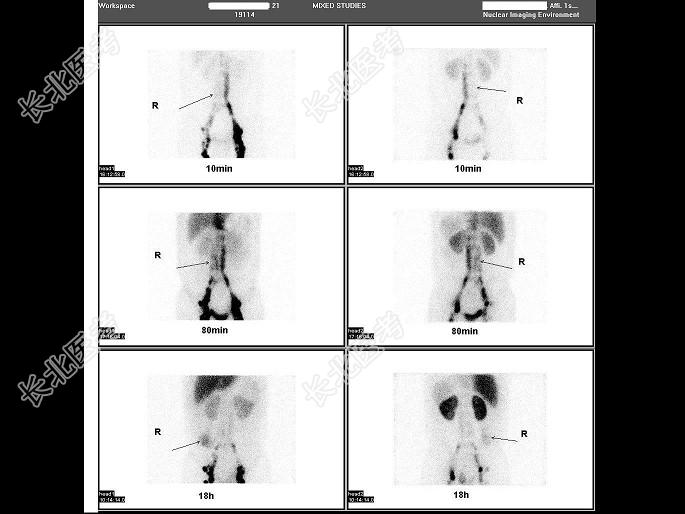

- 单项选择题21岁男,既往有丝虫病史, 行99Tcm-DX显像如图,正确的诊断为 ( )

A、乳糜尿

B、乳糜胸

C、右淋巴导管阻塞

D、乳糜腹

E、以上都不是